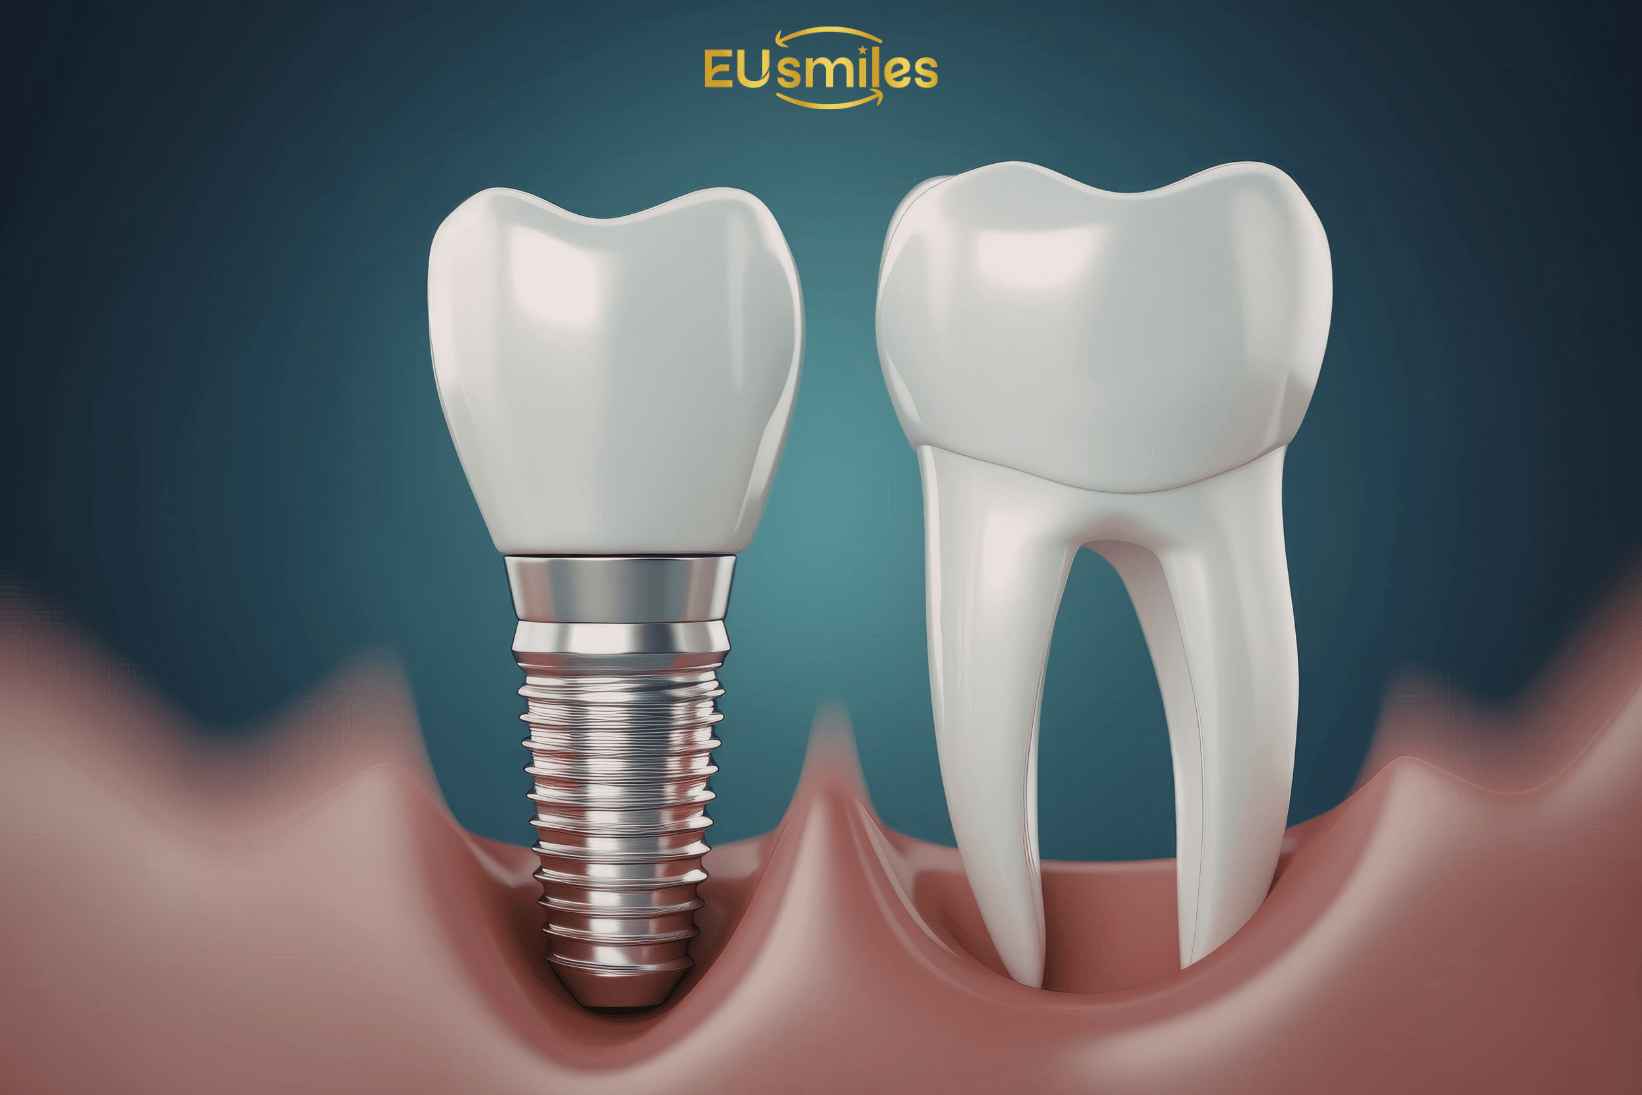

Процедура начинается с диагностики, включая рентген и 3D-сканирование для оценки состояния костной ткани. После этого в челюсть вживляется титановый имплант, который через несколько месяцев срастается с костной тканью, создавая прочную основу для будущего зуба.

Титановые импланты

Титановые импланты считаются классическими в стоматологии, так как они обладают высокой прочностью и совместимы с тканями организма, минимизируя риск отторжения.

Циркониевые импланты

Циркониевые импланты популярны из-за их эстетических свойств, так как они похожи на натуральные зубы. Они идеальны для пациентов, которым важен внешний вид.

Имплантация зубов — это процесс установки искусственного корня зуба в челюстную кость, на который затем устанавливается коронка. Процедура состоит из нескольких этапов: диагностика, вживление импланта, заживление и установка коронки. Для успешной имплантации важно, чтобы костная ткань была в хорошем состоянии. Процесс обычно длится от нескольких месяцев до полугода.

Наиболее популярными материалами для зубных имплантов являются титан и цирконий. Титановые импланты прочны, устойчивы к коррозии и хорошо приживаются в костной ткани. Циркониевые импланты более эстетичны, так как они не видны через десну и подходят для пациентов с высокими эстетическими требованиями.

- Установка импланта: Процесс вживления искусственного корня в кость.